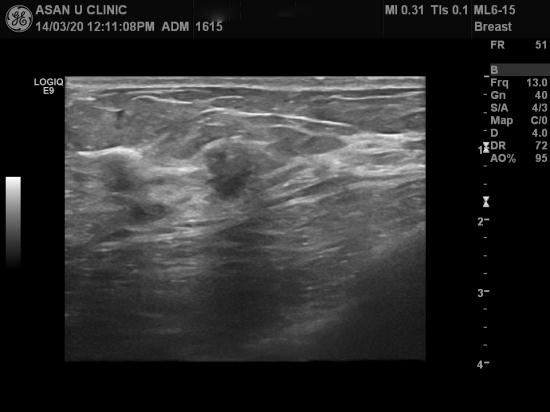

아산유외과 개원 후 79번째 유방암진단.

건강검진상의 이상소견으로 의뢰된 45세 여성분입니다.

우측유방 12시와 1시 인접부위에 1cm미만의 두개의 혹있어

중심핵생검을 실시하였으며

조직검사결과 침윤성 소엽암으로 진단되셨습니다.

모유의 통로가 되는 유관에 흔히 유방암이 생기지만

모유를 만드는 공장역할을 하는 소엽에서도 드물게 발생합니다.

혹의 크기가 작고

겨드랑이 림프절 비대소견이 없어 높은 완치율이 예상됩니다.